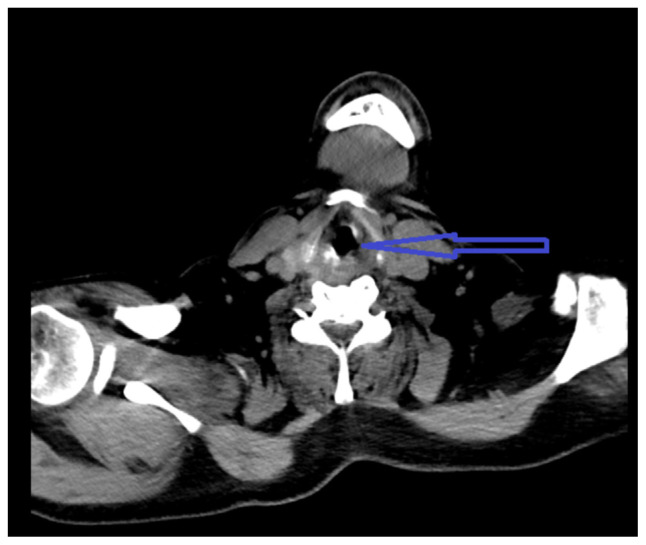

Transesophageal echocardiography is a relatively safe procedure; however, there are rare complications associated with it. Multiple attempts during TEE can lead to injury of hypopharyngeal or parapharyngeal wall leading to an infection. Here, we describe a case of hypopharyngeal-parapharyngeal abscess resulting from multiple TEE attempts during cardioversion leading to a prolonged hospital course.